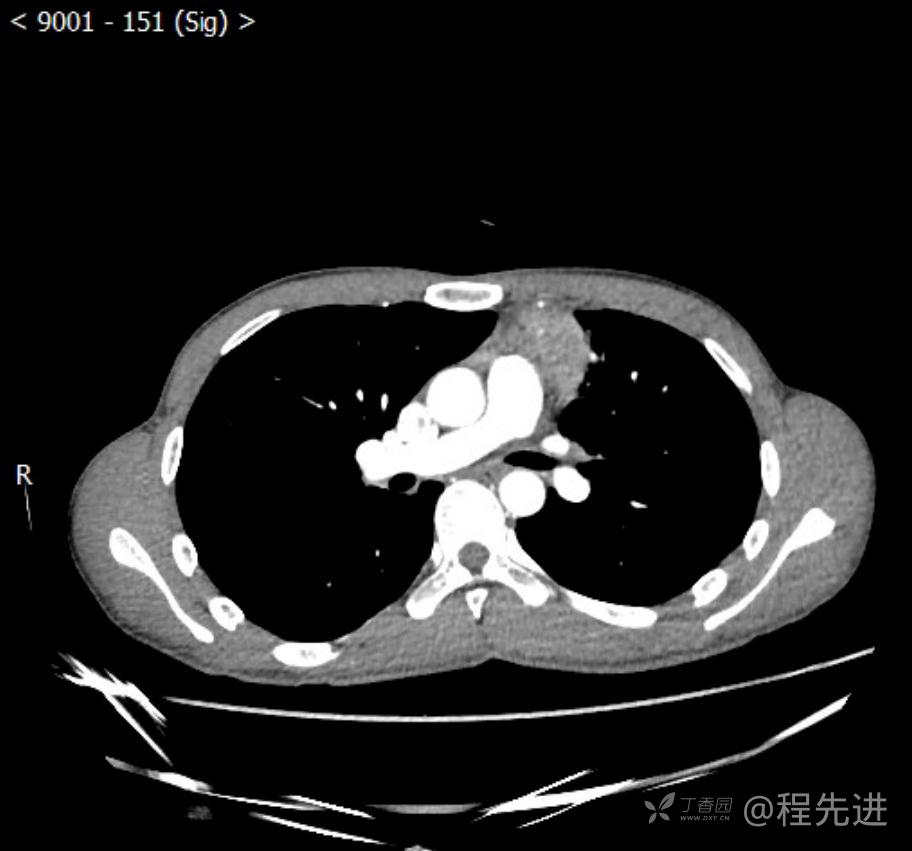

主诉:反复咳嗽1月,发现“纵隔”占位半月,乏力10余天。

现病史:患者1月前无明显诱因出现咳嗽,以夜间为著,伴有少量白痰,无发热,无胸痛、咯血,无痰中带血,未予重视,半月前外院行胸部CT检查发现“左前上纵隔”占位,未予进一步检查及治疗。近10余天自觉乏力,逐渐加重。